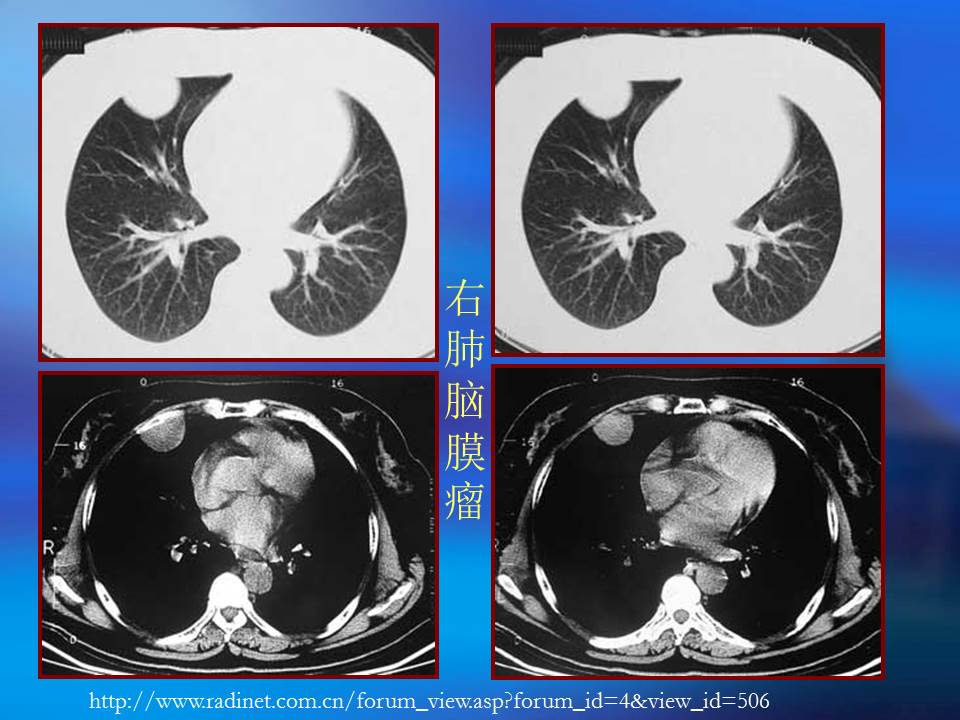

肺良性肿瘤